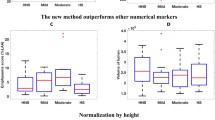

Figure 3a shows that the proxy for inspiration level during the CT scans was correlated with D950 but not with D’15, D’25, or D’35 in the analyses of all scans (n = 170, all dots) and the better-quality scans (n = 144, only blue dots). The LAA% and %DLCO (Fig. 3b and c) and the 15th percentile (Additional file 1: Figure S2) were correlated with D950, D’25, and D’35, but not with D’15. Table 2 summarizes correlation coefficients between CT indexes and pulmonary function in COPD in the analysis of 144 COPD patients with better-quality scan (the proxies for inspiration were > 0.8 and < 1.2). Multivariate regression analyses in Additional file 1: Table S1 showed that D’15, D’25, and D’35 were associated with %DLCO and DLCO/VA independently of LAA%, whereas D950 was not.

Associations of the fractal dimensions with a proxy for inspiration level at CT scan, LAA%, and diffusion capacity. a A proxy for inspiration indicates the degree of the inspiration level during a CT scan that was obtained as a ratio of CT-derived total lung volume (CT-TLV) to physiologically-measured total lung capacity (TLC). This proxy correlated with D based on a fixed threshold of − 950 HU (D950) but not with D based on a threshold of the 15th, 25th, and 35th percentiles of a CT density histogram. b An increase in percent low attenuation area (LAA%) and (c) a decrease in the diffusion capacity of carbon monoxide (%DLCO) were correlated with reductions in D950, D’25, and D’35, but not D’15. Blue dots indicate the 144 cases with better-quality scans defined as those with the proxies for inspiration > 0.8 and < 1.2. Rall and Rsub indicate coefficient correlations for the analysis of all scans (n = 170) and the subanalysis of the better-quality scans (n = 144), respectively. * p < 0.05 and ** p < 0.01